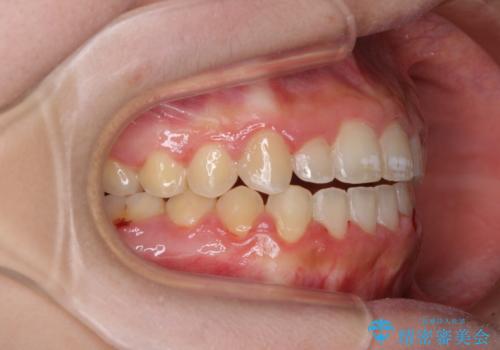

- 前歯のデコボコと、下顎の変位と受け口を気にして来院された患者様です。

初診時には大学病院にて顎の骨を切る外科矯正を勧めましたが、妥協的なゴールでも構わないので外科処置をせずに矯正を行いたいとのことでした。

まずは急速拡大装置にて上顎骨を側方に拡大し、インビザラインにて歯列と咬合を整えることとしました。